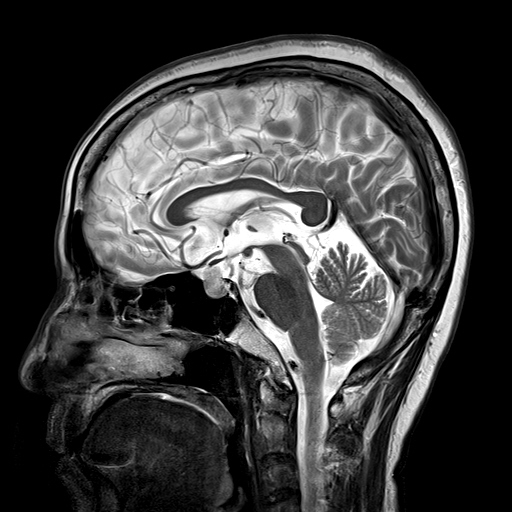

»çÁøCT/MRI